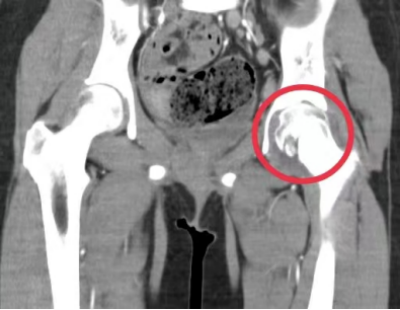

“入院时,患者左髋关节压痛明显伴活动障碍,立即为她完善了相关检查,关节MRI提示感染性病变,髋关节CT提示多发虫蚀样骨质破坏,肺部CT提示肺部多发结节样病变并钙化形成,不排除结核,结核菌素皮肤试验强阳性,γ-干扰素释放试验(T-SPOT)阳性,结合病史,进一步安排了关节穿刺并组织活检,病理证实为髋关节结核。”据儿科副主任、副主任医师周海依介绍,明确为左侧髋关节结核、原发性肺结核后,医护团队为孩子制定了抗结核治疗计划,经过精心的治疗和细致的护理,琪琪的病情好转,疼痛的症状逐渐得到控制,目前仍在住院接受治疗。

(左髋关节CT提示左股骨头多骨质破坏)

“骨结核或关节结核前期症状多为疼痛、肿胀、局部功能障碍、关节畸形等,大多数继发于肺结核,是由结核菌侵入骨或关节引起的化脓性破坏性改变,影像学上呈现虫蚀样改变。人体大部分骨骼,尤其是承重骨或关节(脊柱、髋关节、膝关节等),均可被结核菌‘吞噬’。”周海依介绍,该病病程长,常伴有碎骨、死骨、脓肿、瘘管形成甚至功能障碍,严重者出现截瘫,影响孩子们的学习与生活质量。她表示,结核病虽然“可怕”,但其实是“可防可治”的,一旦发现有结核病,一定要进行正规的治疗,骨结核的治疗周期约18-24月,同时还要配合合理的功能训练防止长短腿、关节功能障碍及肌肉废用性萎缩等。